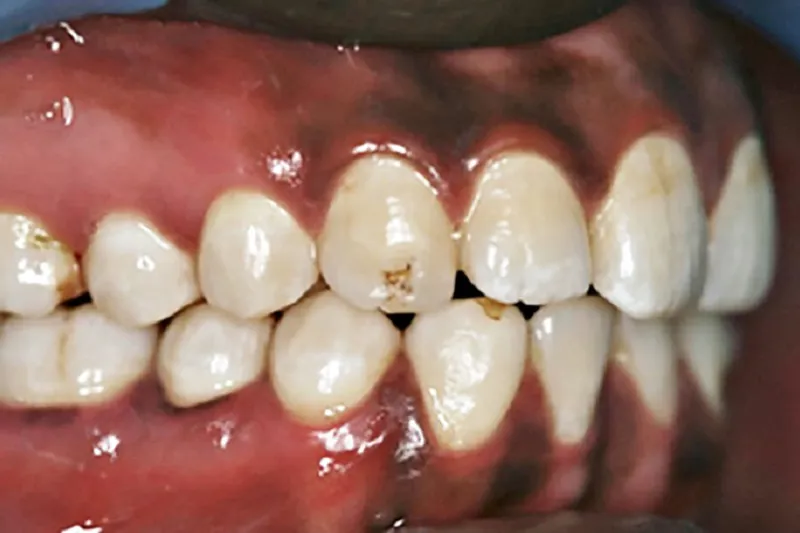

Denne artikel fokuserer på et spørgsmål, som i sagens natur først for relativt nylig er blevet aktuelt i de nordiske lande, nemlig om en øget etnisk mangfoldighed i befolkningen også afspejles i den orale sundhedstilstand og i ændrede manifestationer af orale sygdomme.

Vi præsenterer nogle af de tilgængelige videnskabelige svar på disse meget relevante spørgsmål, fx de genetiske og sociale faktorer, som påvirker caries og parodontitis.

I de nordiske lande er populationen i dag etnisk blandet, og dette indebærer, at tandplejen må tilpasse sig til den ændrede virkelighed. Ud fra sin etniske og kulturelle baggrund kan patienten have specifikke ønsker med hensyn til tændernes form og farve, andre holdninger til kost og mundhygiejne samt andre madvaner, end vi inden for tandplejen er vant til. Dagens tandpleje kan derfor ikke pr. automatik regne med, at bestemte behandlinger eller ønsker er passende, men må også forholde sig til kulturelle aspekter i forbindelse med behandlingsplanlægningen.